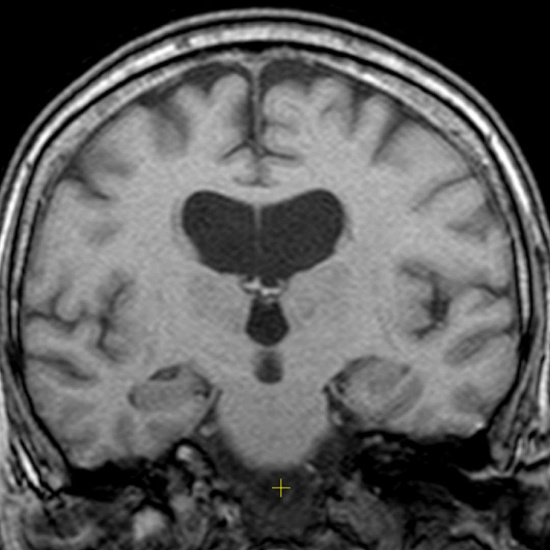

• МРТ ГМ: участок кистозно-глиозного изменения в правой теменной доле. Единичные очаги сосудистого генеза. Изменений в артериях нет. Синусы и внутричерепные вены без особенностей.